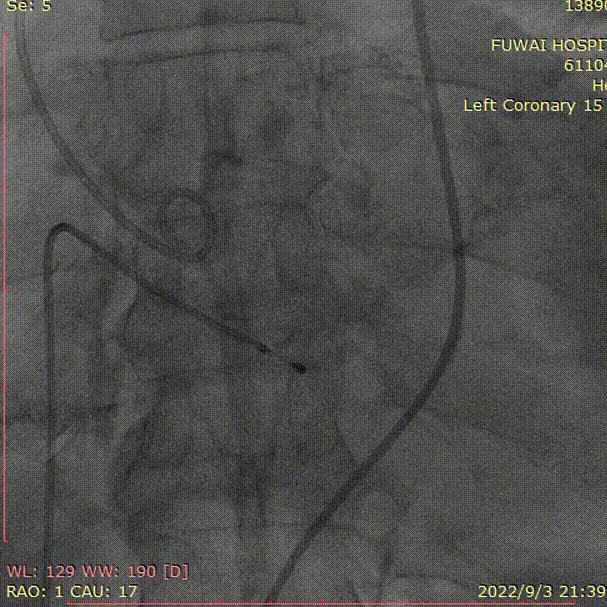

1、冠脉造影和抉择急诊PCI和急诊TAVR

左冠造影